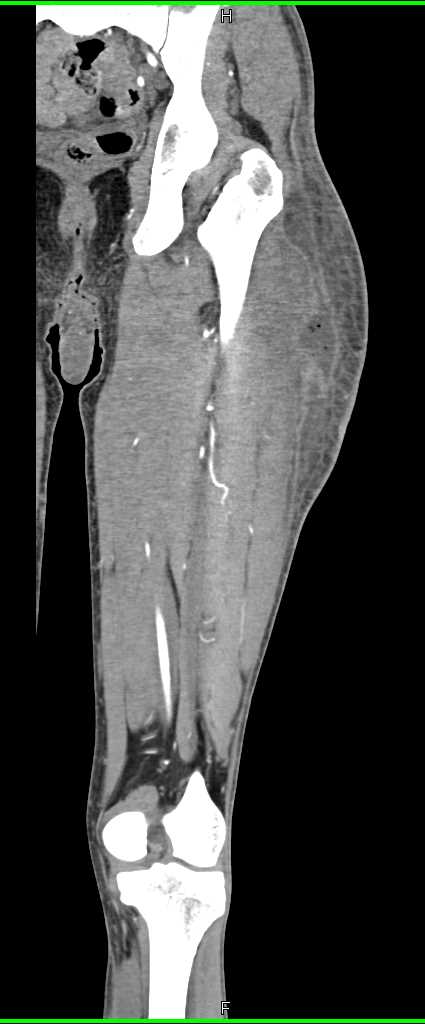

Hematoma Thigh